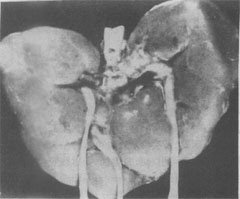

三体(Edwards)综合征的畸形肾

图6-3 18三体(Edwards)综合征的畸形肾

图示马蹄状融合肾及额外输尿管